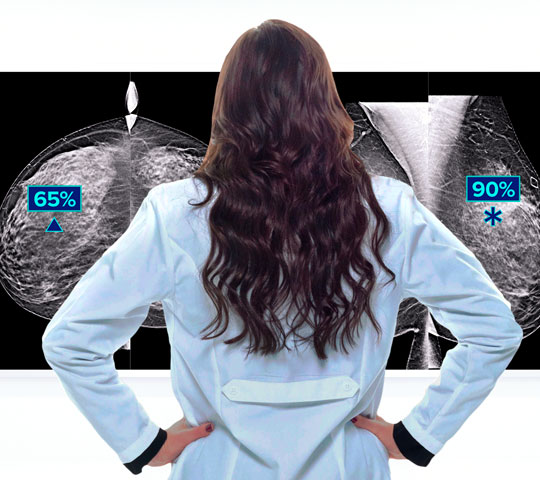

Clinical Performance

Increase diagnostic confidence to help guide the clinical pathway. Studies show contrast-enhanced mammography provides equivalent diagnostic performance to contrast breast MRI.1,2